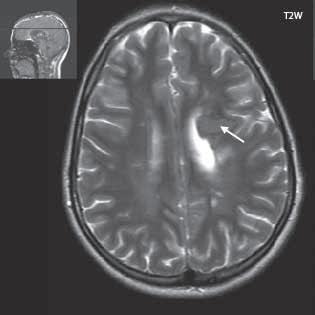

I 5 2 „Fyziologická“ ložiska zvýšeného signálu v T2W obrazu v bílé hmotě mozkové 187

Roztroušená skleróza (RS) 189